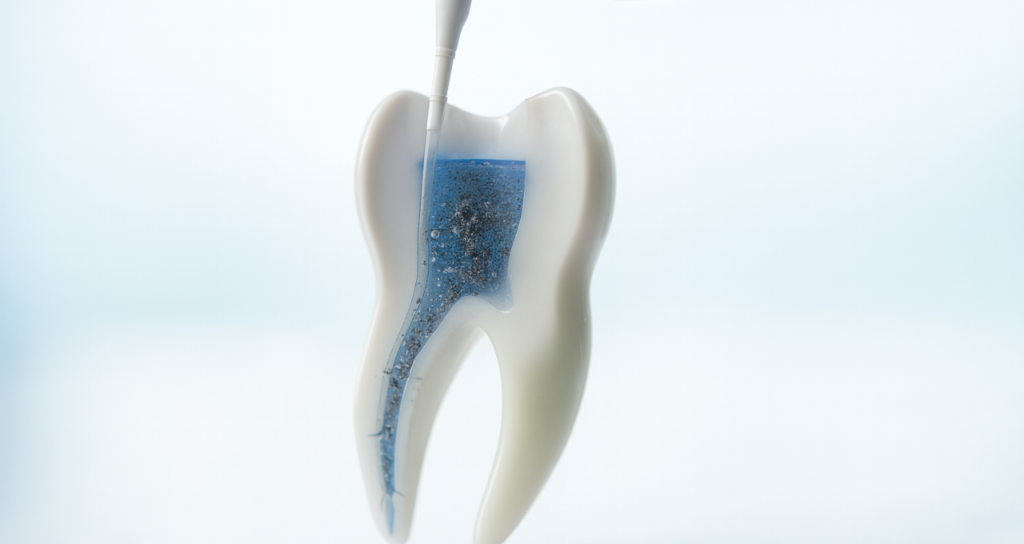

薬液の効果を最大化する「超音波洗浄」

ファイルで物理的に汚れを削り取った後は、薬剤による化学的な洗浄を行います。

しかし、単に薬液を流し込むだけでは、根管の壁にこびりついた削りカス(スミア層)や奥深くに入り込んだ細菌までは除去しきれません。

そこで、当院では「超音波スケーラー」を使用します。

根管の中に満たした洗浄液に超音波の振動を与えることで、キャビテーション(発泡現象)を起こします。

この微細な泡が弾けるエネルギーと液体の対流によって、複雑な根管の隅々まで薬液を行き渡らせ、強力に汚れを洗い流します。

物理的な清掃と化学的な洗浄を組み合わせることで、根管内を徹底的にクリーンな状態にします。